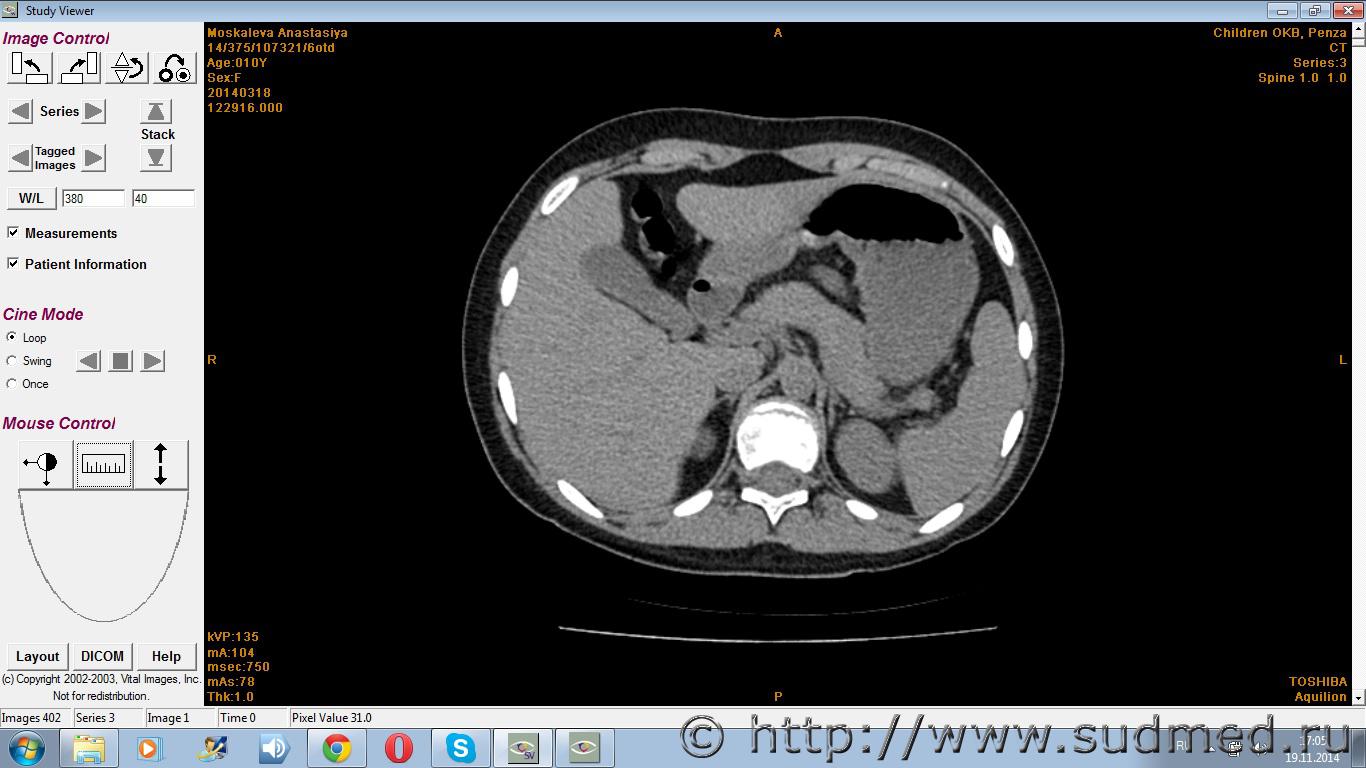

У меня дочь на скалодроме у пала с высоты метров 7.Поставили диагноз компрессионные переломы грудного и поясничного отдела позвоночника.А сейчас судебно-медицинский эксперт говорит,что у неё нет компрессионных переломов,а есть грыжи ранее приобретённые. Дочька до этого занималась только плаваньем.

Есть снимки.

Судя по представленным данным судебно-медицинский диагноз и, соответственно, степень тяжести вреда здоровью определены верно. Достоверных объективных признаков компрессионных переломов позвонков не установлено.

Клиновидная деформация тел позвонков и грыжи Шморля однозначно не свидетельствуют о костно-травматической патологии позвонков.

При необходимости проконсультируйте ВСЕ снимки позвоночника у опытного рентгенолога (лучше - при личном общении, т.к. при передаче через интернет может заметно уменьшаться детализация снимков). При наличии реально существующих оснований (оптимально - письменно выраженное мнение рентгенологов о достоверных признаках "свежих" переломов позвонков) - ходатайствуйте о назначении повторной суд-мед.экспертизы с включением в состав экспертной комиссии высококвалифицированных рентгенологов, детских травматологов-ортопедов, неврологов.